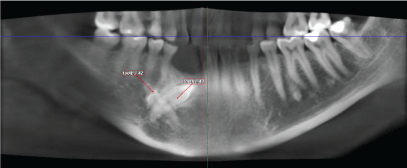

The initial panoramic radiograph revealed impactions of the permanent mandibular right canine obliquely positioned with the crown pointed mesially and lateral incisor with a horizontal position under the first and second premolars and its crown is pointed distally.

Reformatted cropped panoramic view shows that the right mandibular canine (#43) is impacted and the root is fully formed with dilacerations of the tip of the root, the crown is directed mesially (Figure 2).

Figure 2: Reformatted cropped panoramic view of the impacted mandibular right canine and lateral incisor.

There is well defined unilocular radiolucency in the lower anterior area below the crown of impacted tooth #43. This could be OKC or simple bone cyst (Figure 3).